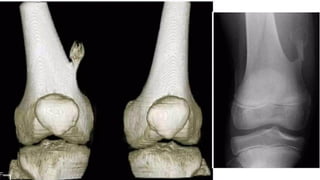

GCT O s t e o c l a s t o m a s

• • L o c a t i o n

• •around the knee: distal femur and proximal tibia: 50-65%

• • distal radius: 10-15%

• • sacrum: 4-10%

• • vertebral body: 5-10%

• A lucent lesion typically situated beneath the articular surface

• E c c e n t r i c

• Narrow z o n e o f transition

• 'soap-bubble' pattern of calcification

• No sclerotic margin

• • overlying cortex is thinned, expanded or deficient

• • Soft-tissue mass may be present

• • No calcification or ossification until complicated by f r a c t u r e

• • CT Scan & MRI

• • To delineate soft tissue extension

• • B o n e s c a n

• • Increased activity in blood-pool phase

Plain film & CT features